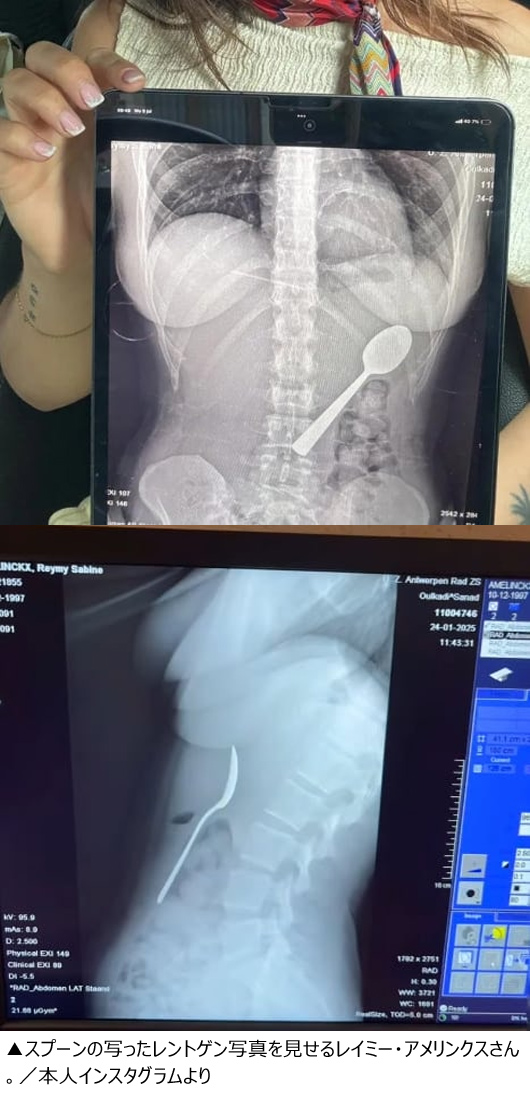

【写真】レントゲン写真を見せるレイミー・アメリンクスさん(28)

検査したところ、スプーンが大きすぎて自然に排出することが困難な状態だった。撮影されたレントゲン写真には、レイミーさんのおなかの中にスプーンが垂直に引っかかっている様子がはっきりと写っている。